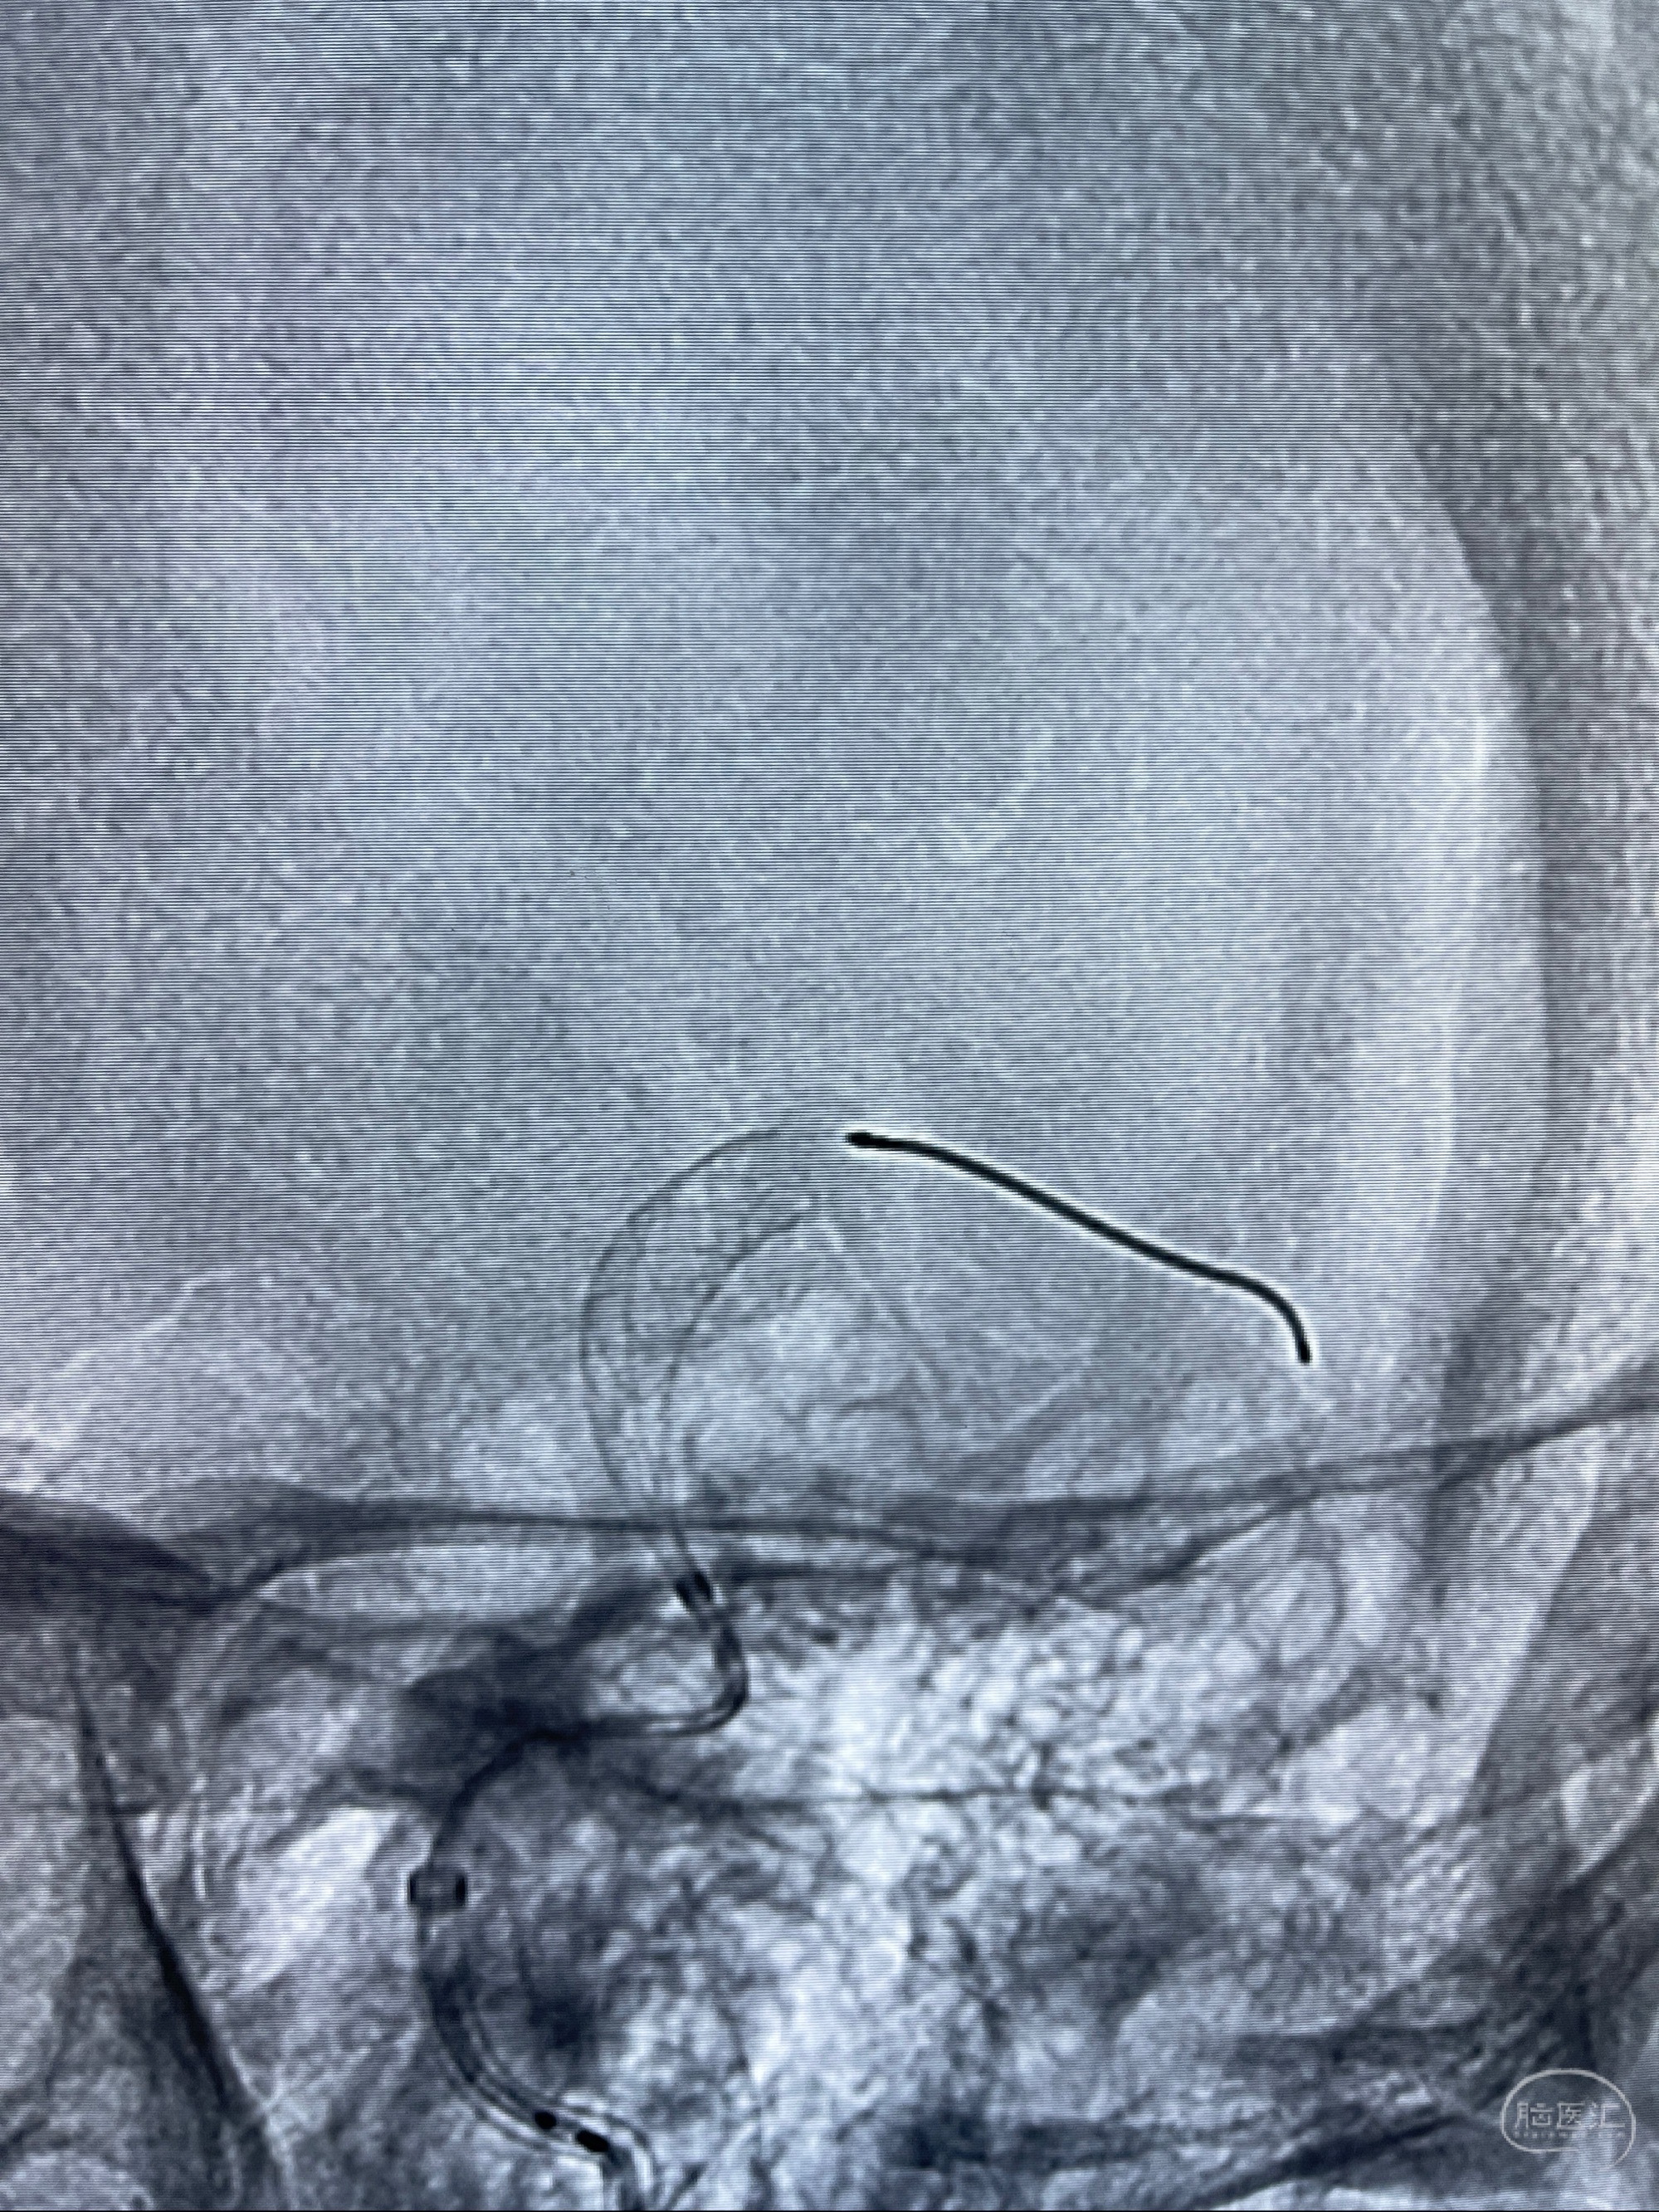

2023-07-27全脑血管造影:双侧颈内动脉眼动脉段动脉瘤,右侧较大

2023-08-01全麻下行双侧颈眼动脉瘤支架辅助栓塞

- pipeling4.5-20mm

- pipeline 4.0-20mm